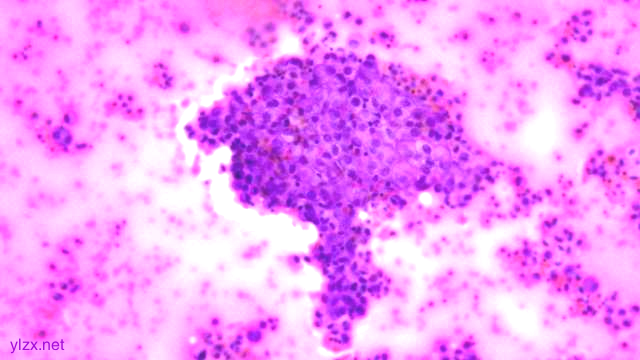

镜下:

HE:

黏膜间质内见胞浆丰富,红染及粉染瘤细胞弥漫分布,部分细胞核稍偏位,核圆形,稍增大,深染,见核仁,穿插在固有腺之间,伴少量炎细胞浸润。

瘤组织穿插在固有腺之间,较弥漫,核稍增大,深染

瘤细胞稀疏排列,胞浆粉染及红染,宽阔

瘤细胞核圆形,见核仁,部分细胞核偏位,未见核分裂象

瘤细胞核仁明显